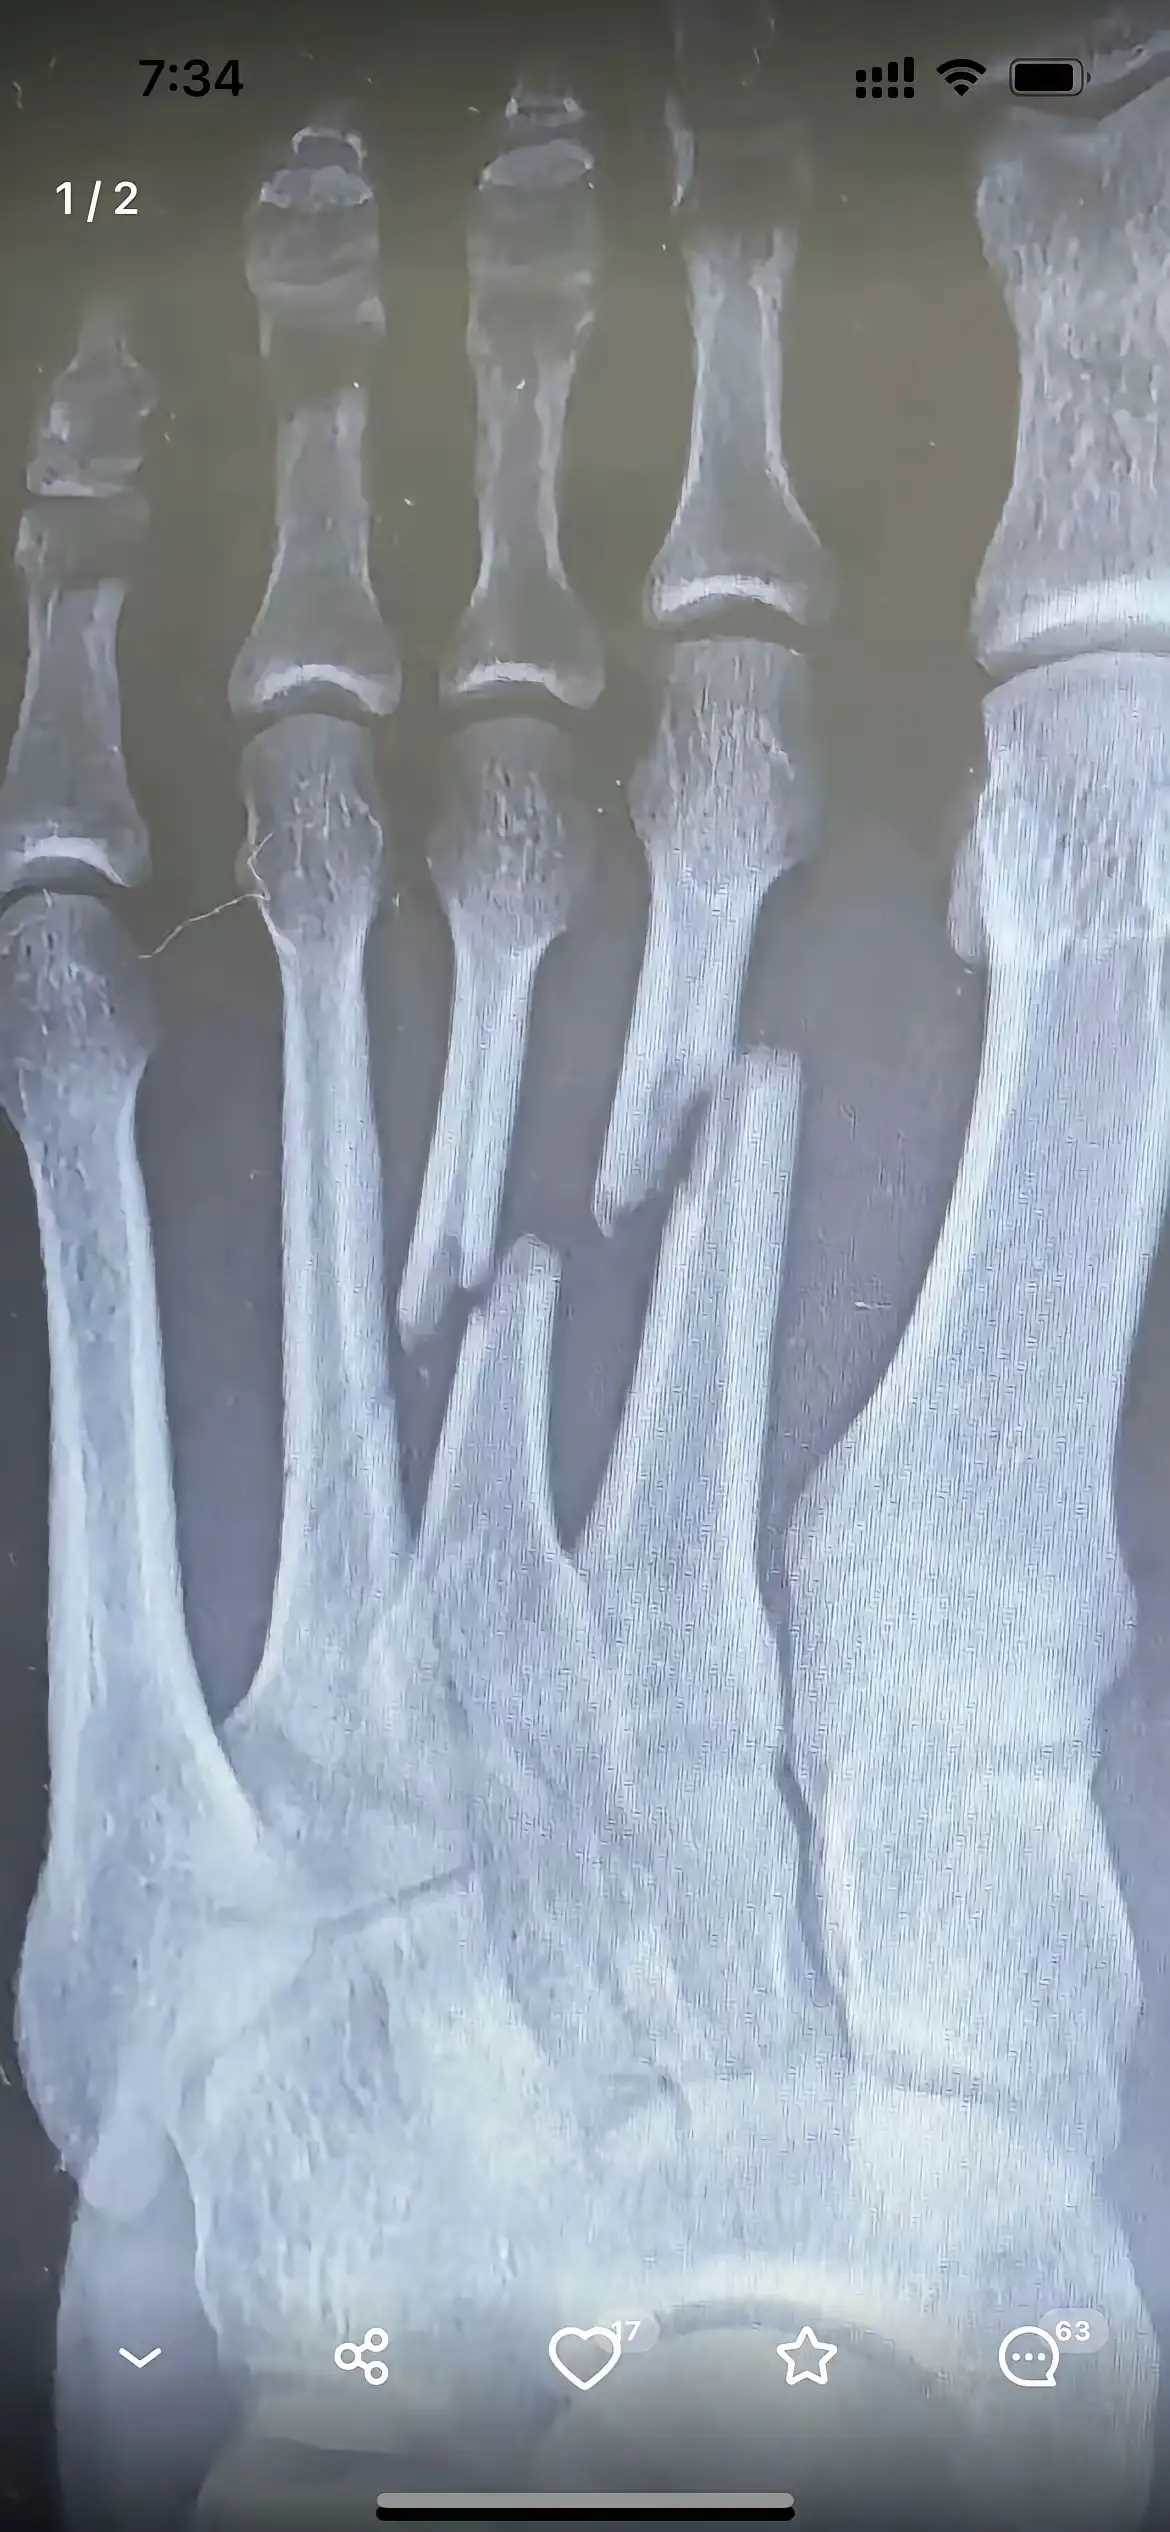

那張X光片靜靜躺在醫生手中,清晰顯示著第三蹠骨的斷裂與錯位——這是李阿嬤三個月前拒絕手術時留下的影像。當時,家人們圍在病床邊心急如焚:「媽,這骨頭都錯位了,不開刀會落下終身殘障的!」

三個月裡,兒女們每日提心吊膽。看著母親腫脹未消的腳踝,看著那明顯凸起的部位,他們已做好照顧殘障老人的準備。直到復查那天,新的X光片讓所有人都愣住了——原本錯位的斷骨,竟在未手術的情況下,奇跡般地長合在一起了。

「這……」醫生推了推眼鏡,仔細比對著新舊兩張片子,「雖然癒合處有輕微隆起,關節面也略顯不平,但確實自然癒合了。」他指著片子解釋:「人體骨骼本身就有強大的自愈能力,手術的鋼釘鋼板只是幫助復位,真正讓骨頭連線的,還是身體自身的成骨細胞。」